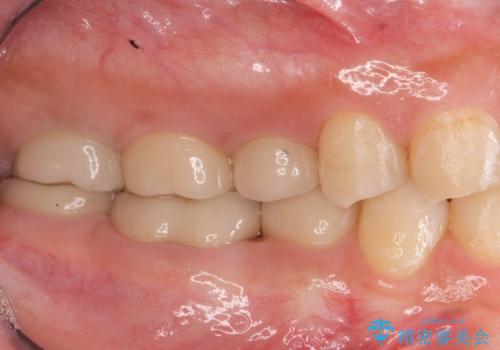

歯周外科を行うことで、歯ぐきの位置を下げ歯の高さを作り出し安定したクラウンの装着が可能となります。また同時に舌の邪魔となっていた骨隆起の除去を行うこととしました。

- 37.4万円(ジルコニアクラウン×2・仮歯×2・歯周外科手術)費用は治療当時の料金となります